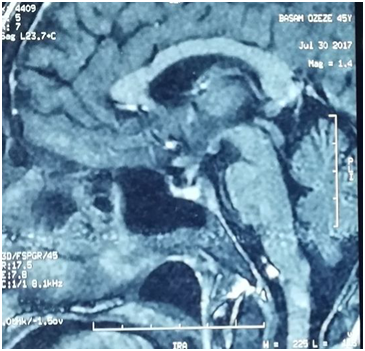

The patient's labs level was within normal except for CRP was elevated. By three separated measurement (one hour between each), water deprivation test revealed increased serum osmolality, increased serum Na+ and decreased urine osmolality. Hormonal Laboratory tests showed decreased FT4 and Testosterone. Magnet Resonance Imaging of pituitary gland was normal and no abnormality was detected (Figure 1). Chest X-ray showed diffuse interstitial reticular densities in both pulmonary fields (Figure 2). X-ray of pelvis and legs showed lytic lesions.

Pituitary involvement is more common in systemic disease. The hypothalamic-pituitary axis is rarely a primary site of Langerhans cell histiocytosis involvement. The most common site of CNS involvement in LCH is the hypothalamic-pituitary axis, which results in diabetes insipidus in 10-50% of patients.2 In our case, the initial manifestation was polydipsia and polyuria. Presumptive diagnosis of Diabetes Insipidus was made clinically by giving the patient "desmopressin" due to the inability to do a lab tests and MRI for pituitary gland because the patient was living in a war zone. 3 years later when the patient could seek Aleppo University Hospital, we performed water Deprivation test and MRI for pituitary gland to confirm the diagnosis.